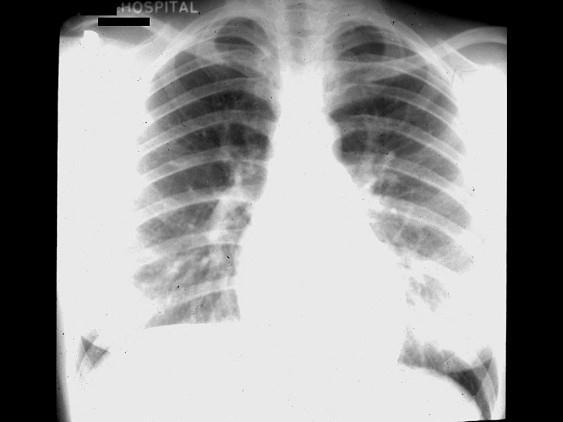

问题 男,12岁,体检时发现心脏有杂音。在胸骨左缘第二肋间闻及ⅡⅢ级收缩期喷射性杂音,未扪及震颤,P亢进。胸片如图,示梨形心,右心房,右心室增大,肺动脉段饱满,主动脉结小,肺纹理增多。EKG示电轴右偏,V1呈Rsr’型,最可能的诊断是 ( )

选项 A、动脉导管未闭 B、肺动脉狭窄 C、房间隔缺损 D、法洛四联症 E、室间隔缺损

答案 C